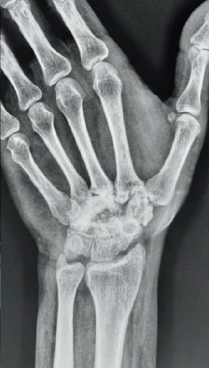

Aneurysmal Bone Cyst of Lateral Cuneiform: Challenge in Diagnosis and Management

Purushotham Lingaiah , A R Nataraj ………………………………p.233-237